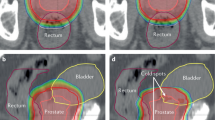

We examined skin color in terms of L*, a*, b* values. The average (±standard deviation) of L* (a*, b*) value was 65.3 ± 2.45 (6.02 ± 1.48, 16.7 ± 1.74) for a treated breast and 67.17 ± 2.70 (5.24 ± 1.25, 16.1 ± 1.67) for an untreated contralateral breast [n = 72, p < 0.0001 (p = 0.0004, p = 0.080)]. This indicated that surgery decreased the L* value (darker) and increased the a* (reddish) value while also possibly decreasing the b* value (yellow). Figure 1 shows a representative image of grade 2 radiation dermatitis.

A representative image of grade 2 radiation dermatitis. A 59-year-old female showed grade 2 radiation dermatitis at 50 Gy/25 fractions of postoperative radiotherapy for left breast cancer (scirrhous carcinoma; pT1cN0M0). Her Δa* value was 2.975 (last a* value = 10, initial a* value = 7.025), whereas ΔL* value was −8.625 (initial L* value = 64.125, last L* value = 55.55).